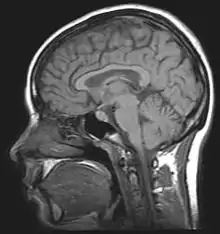

| For the diagnosis, brain scans (such as MRI) should be done to rule out other potential causes. | |

The diagnosis may be suspected on the basis of the history and examination. To confirm the diagnosis, as well as excluding alternative causes, several investigations are required; more investigations may be performed if the history is not typical or the person is more likely to have an alternative problem: children, men, the elderly, or women who are not overweight.[8]

Neuroimaging, usually with computed tomography (CT/CAT) or magnetic resonance imaging (MRI), is used to exclude any mass lesions. In IIH these scans typically appear to be normal, although small or slit-like ventricles, dilatation and buckling[17] of the optic nerve sheaths and "empty sella sign" (flattening of the pituitary gland due to increased pressure) and enlargement of Meckel's caves may be seen.

An MR venogram is also performed in most cases to exclude the possibility of venous sinus stenosis/obstruction or cerebral venous sinus thrombosis.[5][7][8] A contrast-enhanced MRV (ATECO) scan has a high detection rate for abnormal transverse sinus stenoses.[14] These stenoses can be more adequately identified and assessed with catheter cerebral venography and manometry.[15] Buckling of the bilateral optic nerves with increased perineural fluid is also often noted on MRI imaging.